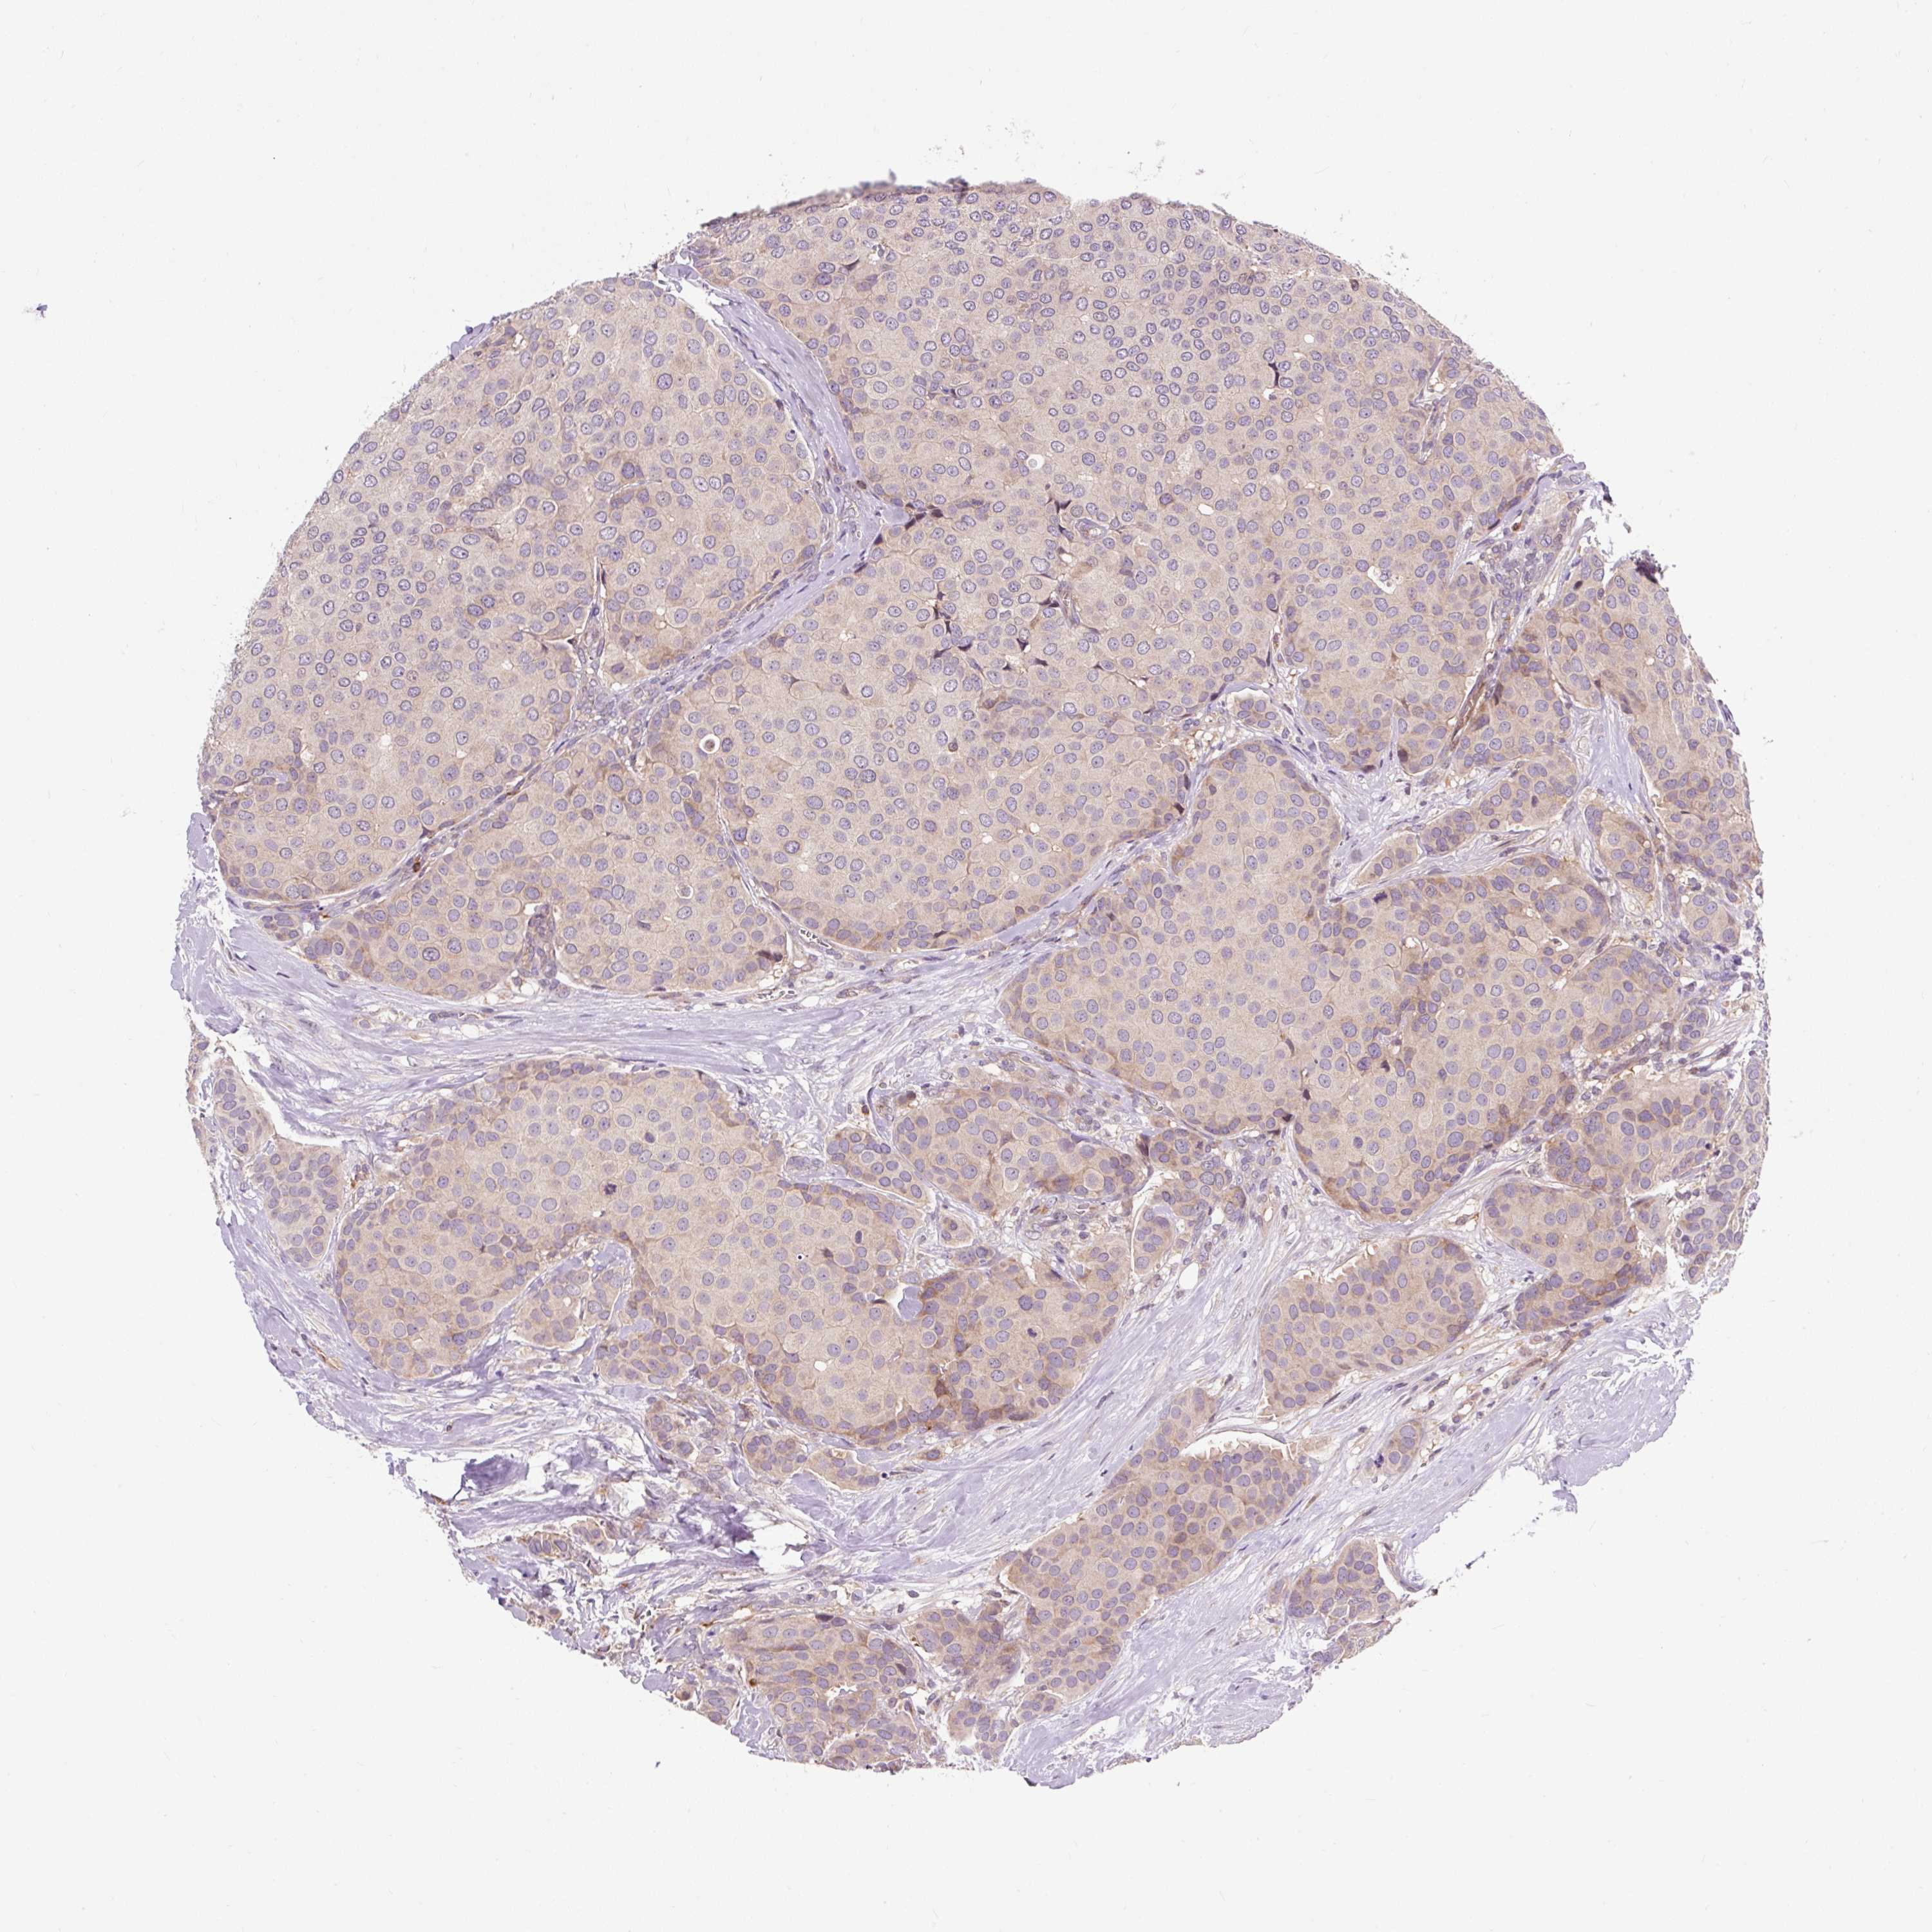

CANCER BREAST CANCER Show tissue menu

BRCA TCGA BRCA VALIDATION PROTEIN EXPRESSION